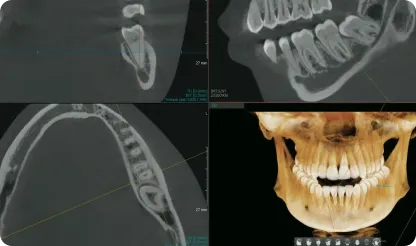

Использование современных ортопантомографов, другого оборудования

Врачи работают с использованием высокоточного диагностического оборудования

Неважно, с каким случаем вы обратитесь, в результате вы получите полную информацию о состоянии полости рта и снимки.